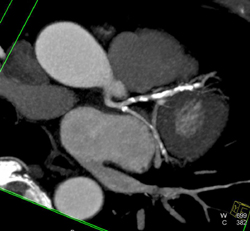

Normal Right Coronary Artery